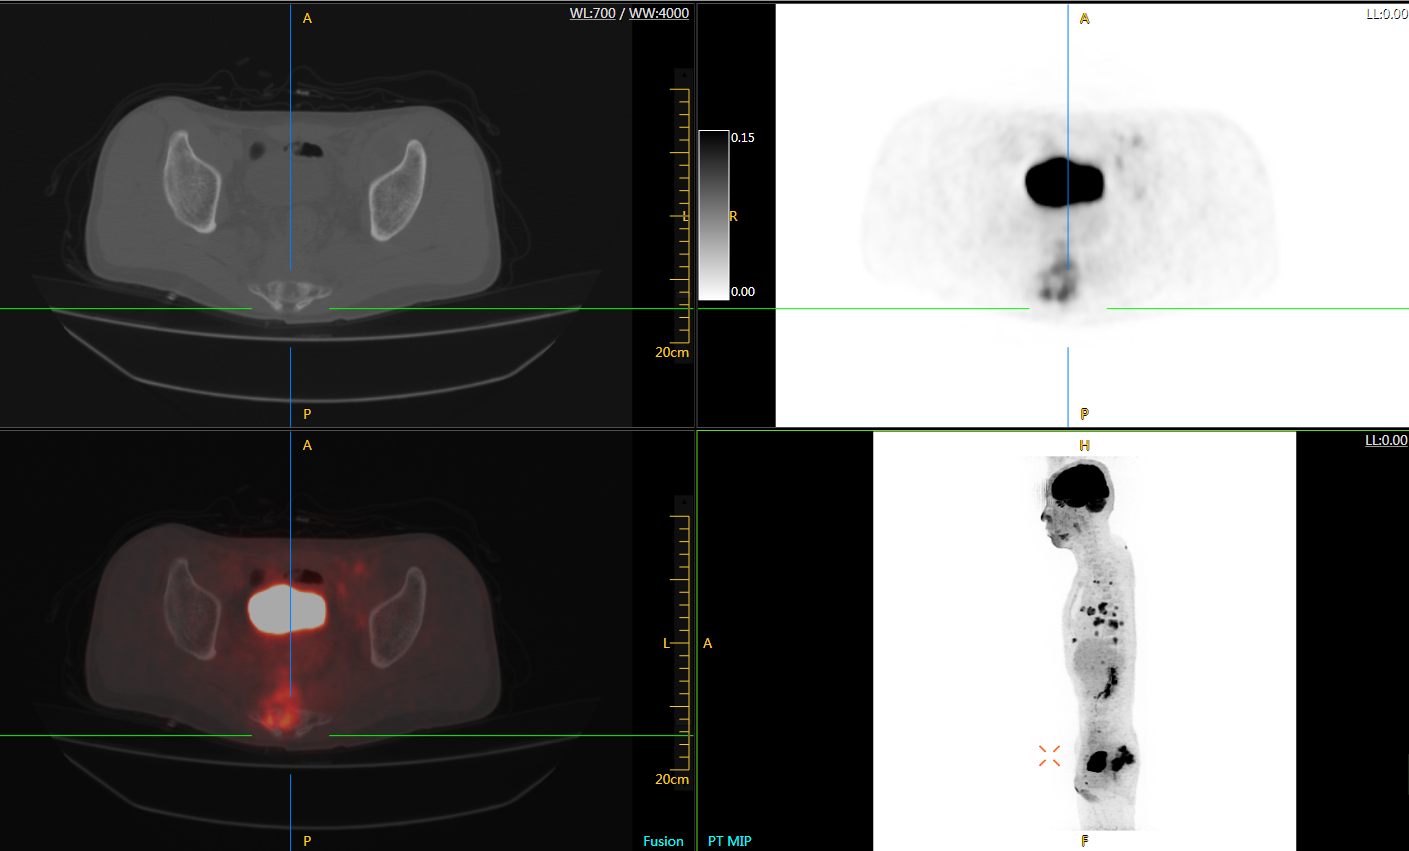

肺癌轉(zhuǎn)移及復(fù)發(fā)

患者男性,66歲,七年前發(fā)現(xiàn)右肺肺癌,其間手術(shù)兩次,共切除兩個(gè)肺葉,復(fù)查;

診斷意見(jiàn),回腸轉(zhuǎn)移,右肺殘留部復(fù)發(fā)